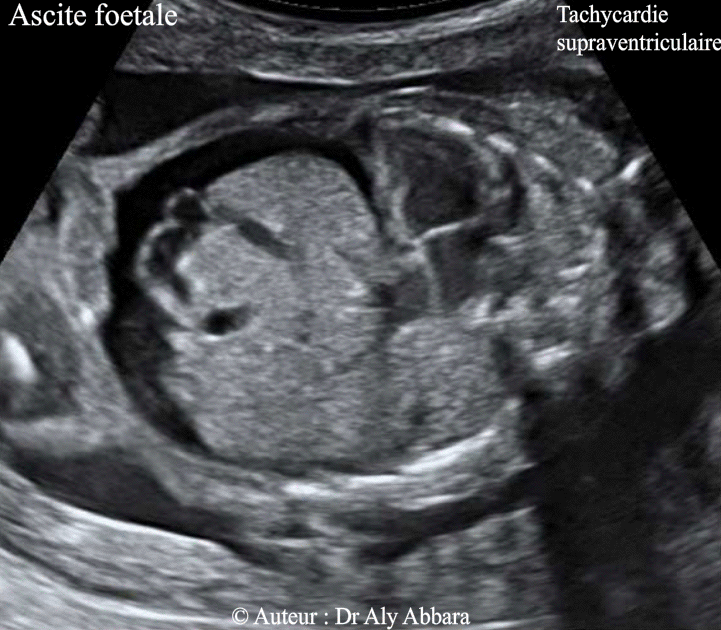

Ascite dans un contexte de tachycardie supra-ventriculaire chez un foetus de 23 SA

• Images échographiques montrant la présence d'une ascite fœtale et d'une spléno-hépatomégalie.

Il s'agit d'un fœtus de 23 SA chez lequel l'échographie montre la présence d'une tachycardie supra ventriculaire fœtale à l'origine d'une insuffisance cardiaque compliquée par une anasarque fœtoplacentaire

: épanchement péricardique ; ascite , hépato-splénomégalie et épaississement du placenta.

• L'étude de la morphologie générale et aussi cardiaque fœtale ne montre pas d'anomalie particulière associée.